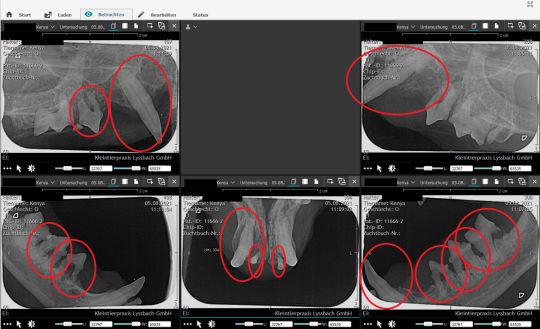

Anschliessend werden die Zähne einzeln befundet und alle vier Kieferquadranten geröntgt. Dabei stellt sich heraus, dass eine Vielzahl von Kau-, Eck- und Schneidezähnen beschädigt oder faul sind.

Zahnröntgen

Im linken Unterkiefer lassen sich beispielsweise zwei verschiedene Krankheitsprozesse erkennen: Der Eckzahn (Zahn 304) weist eine Entzündung des Zahnfachs auf: Der Knochen um die Wurzel des Zahnes ist durch die chronische Entzündung stark aufgetrieben und der Zahn wackelt entsprechend (grüner Pfeil). Die hintere Wurzel des letzten Kauzahns (Zahn 309) ist zerfressen, hier handelt es sich um eine sogenannte FORL-Schädigung (roter Pfeil). Die beiden restlichen Zähne weisen Komponenten beider Erkrankungen auf.